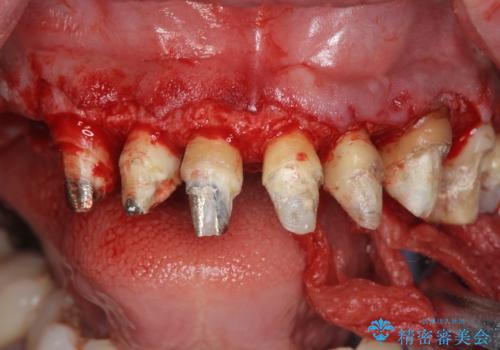

前医により、前歯は歯ぐきの奥深くまで形成されこのままの状態でセラミックをやりかえたとしても歯ぐきの腫れの改善は難しい状況です。

歯周外科を行い歯と歯槽骨・歯肉の関係を是正することで歯ぐきの状態を改善し、将来に亘り安定した歯周環境の維持を期待できるセラミック治療を実践します。